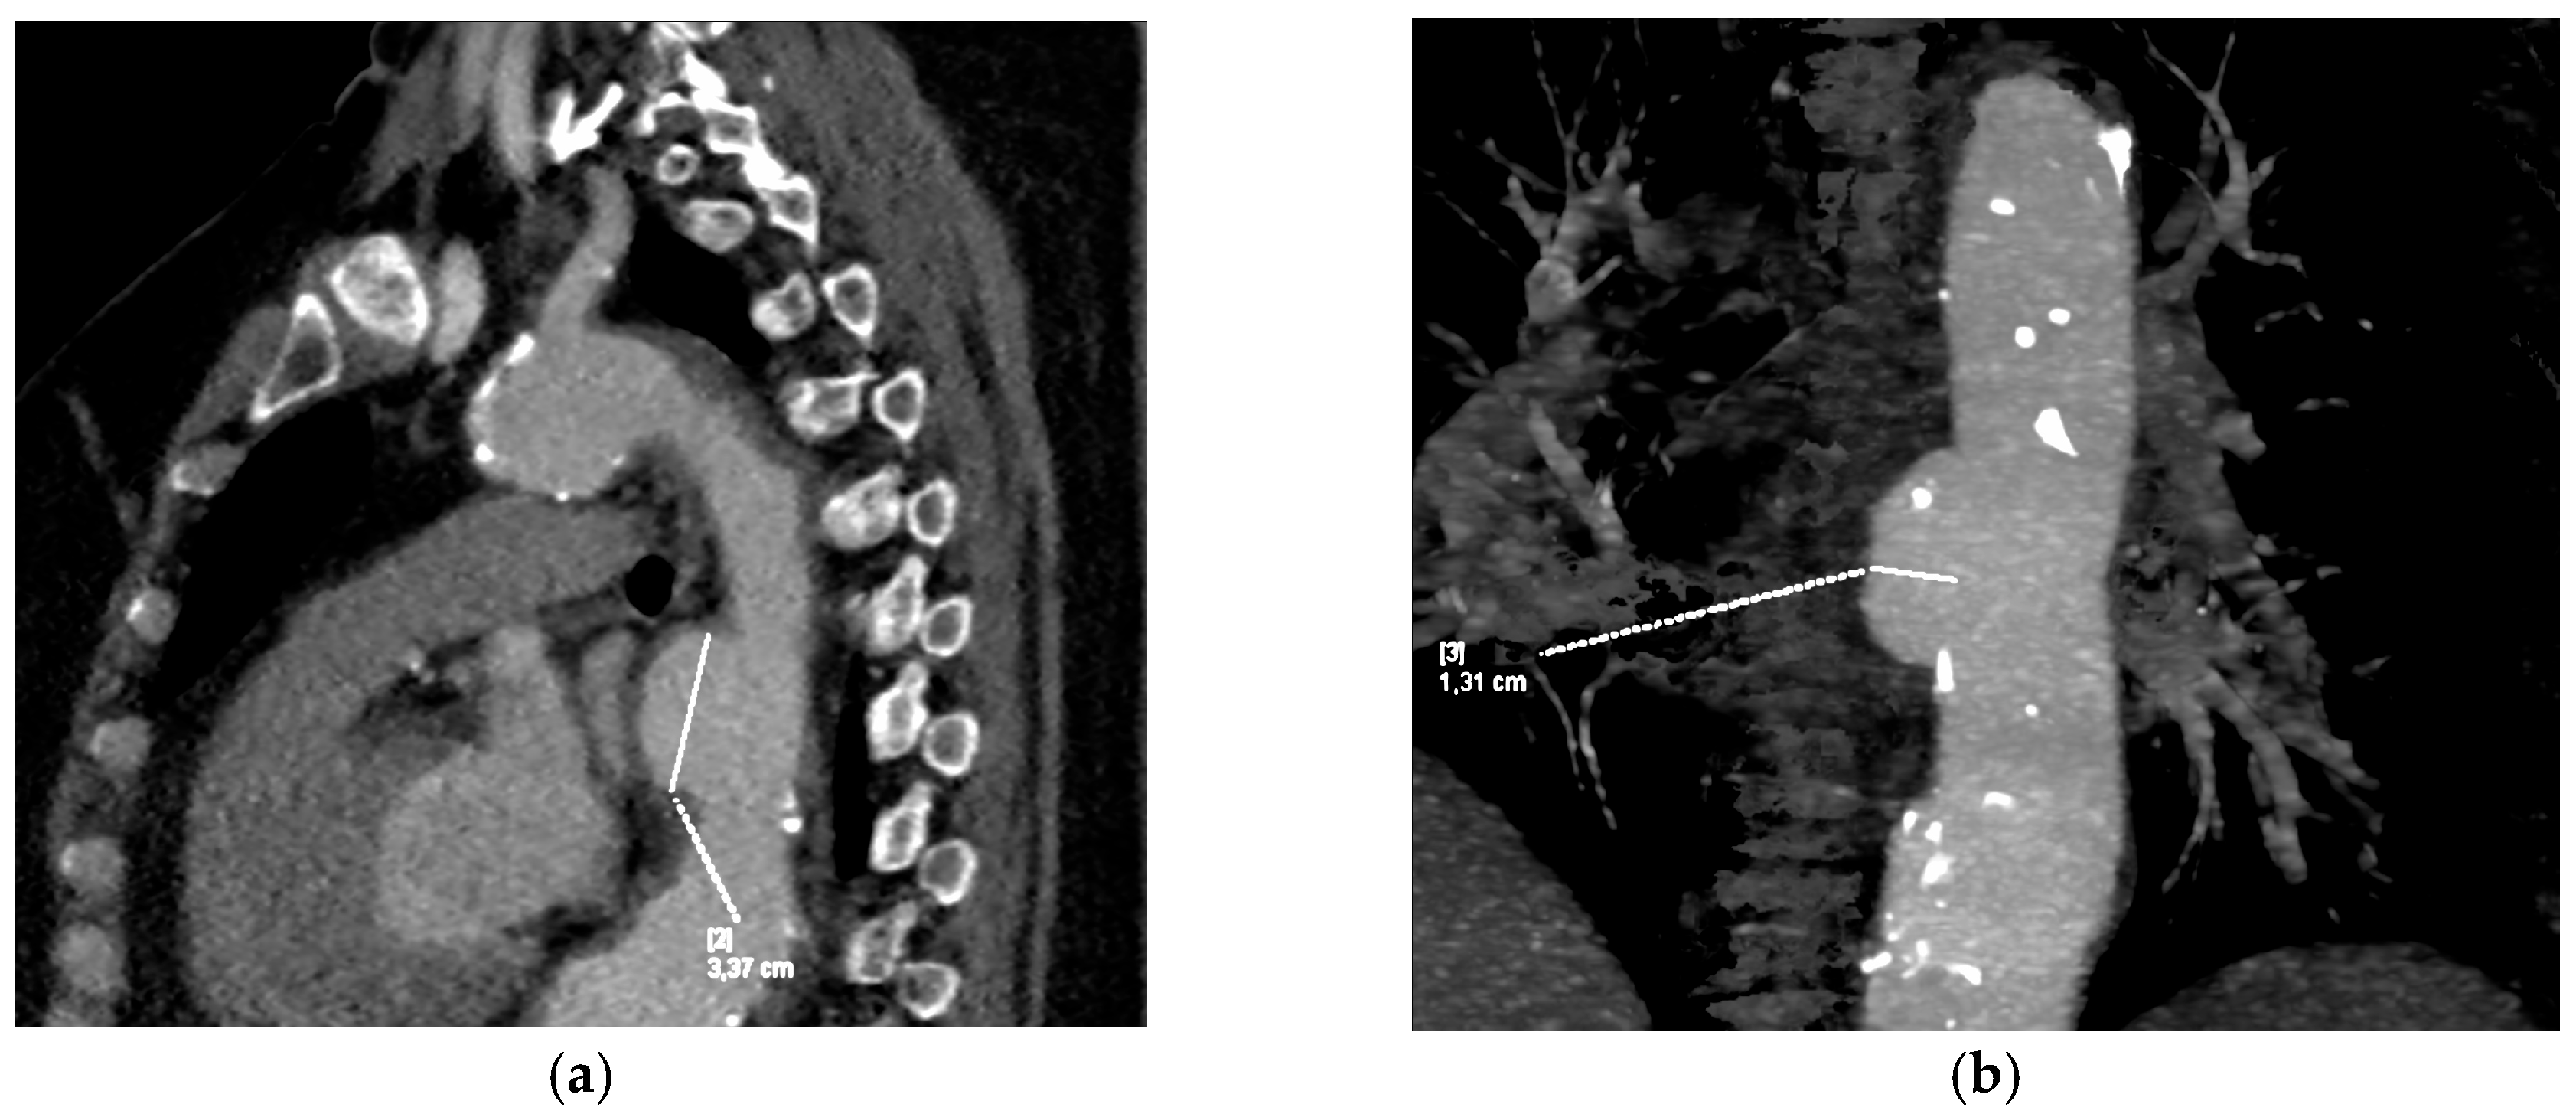

2.2. Imaging